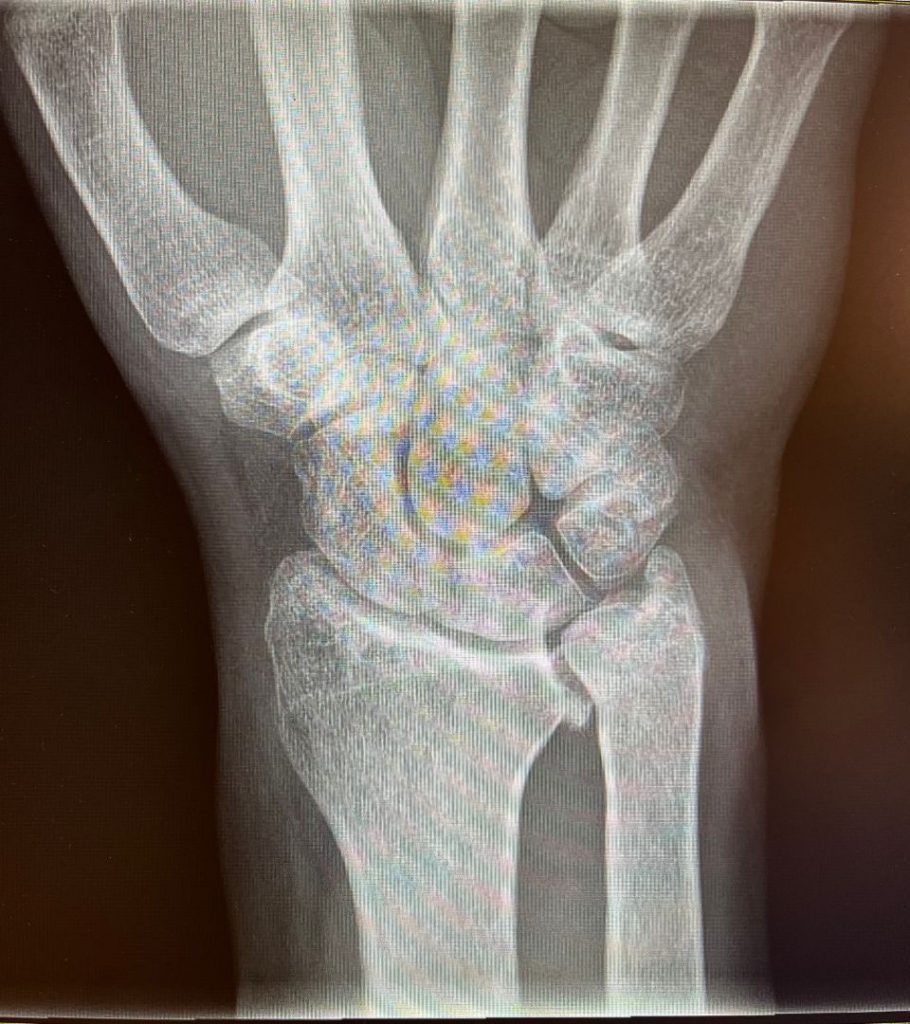

– Síndrome de Impactación Cubital (situación que puede darse cuando el cúbito es más largo que el radio, de manera que impacta o choca en los pequeños huesos del carpo ante determinados movimientos) (Figura 2).

Figura 2- Cúbito plus.